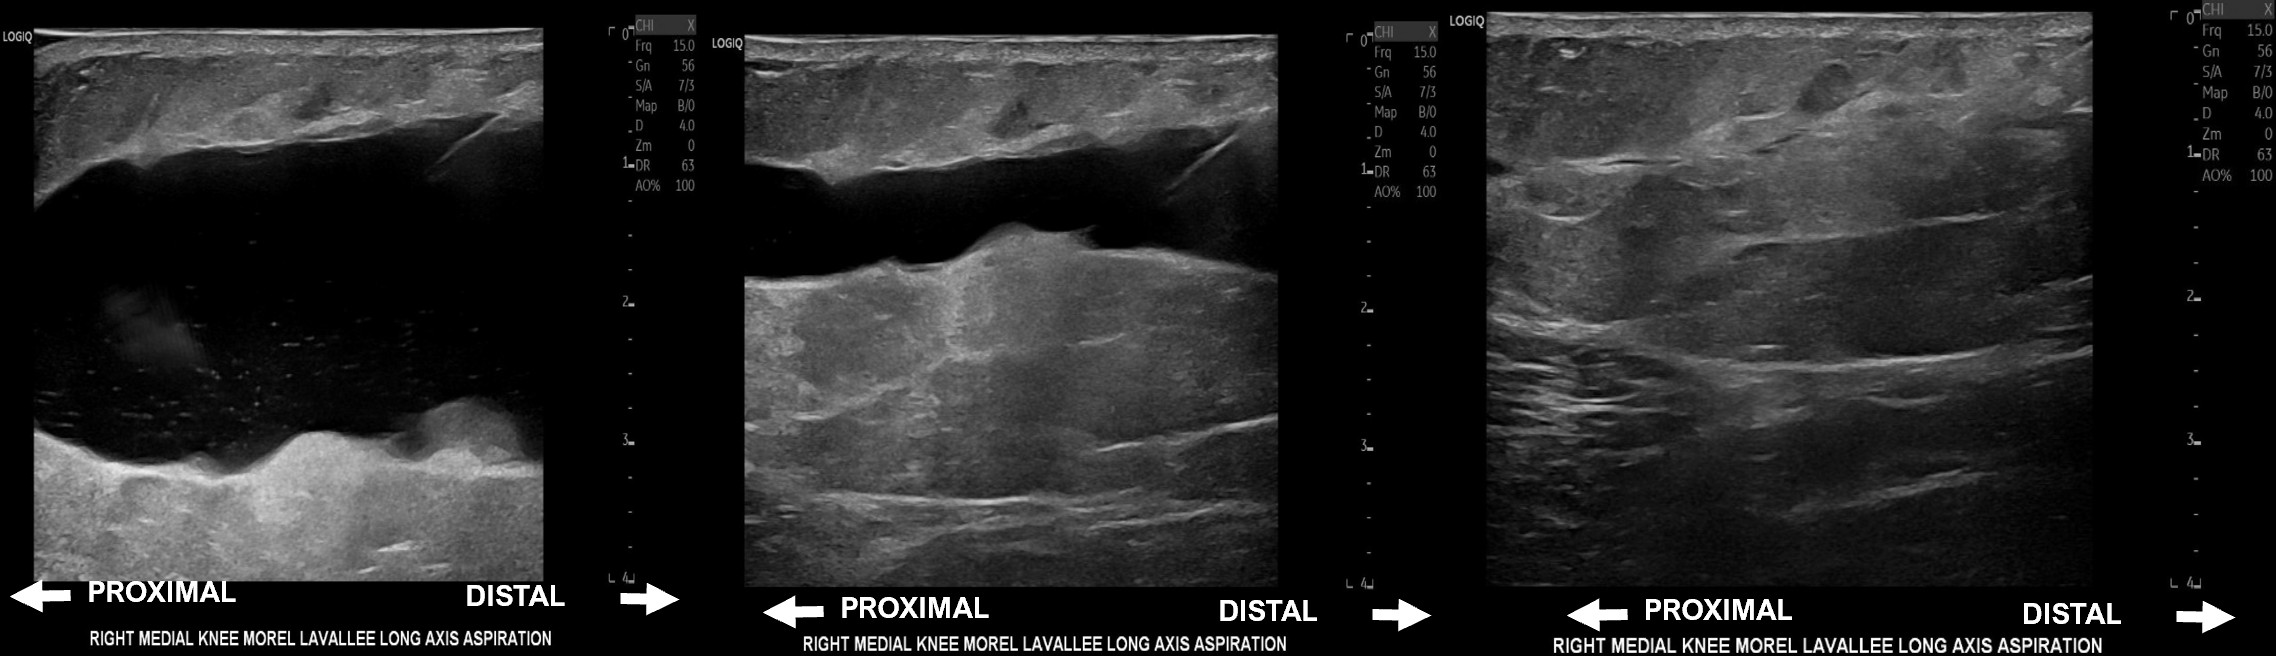

Unlabeled long axis progression of Morel-Lavallee lesion aspiration 17 days after the initial injury yielding 170 mL of serous fluid, followed by corticosteroid injection.

Unlabeled short axis progression of Morel-Lavallee lesion aspiration of 37 mL of serous fluid followed by doxycycline sclerodesis at eight months post-injury.